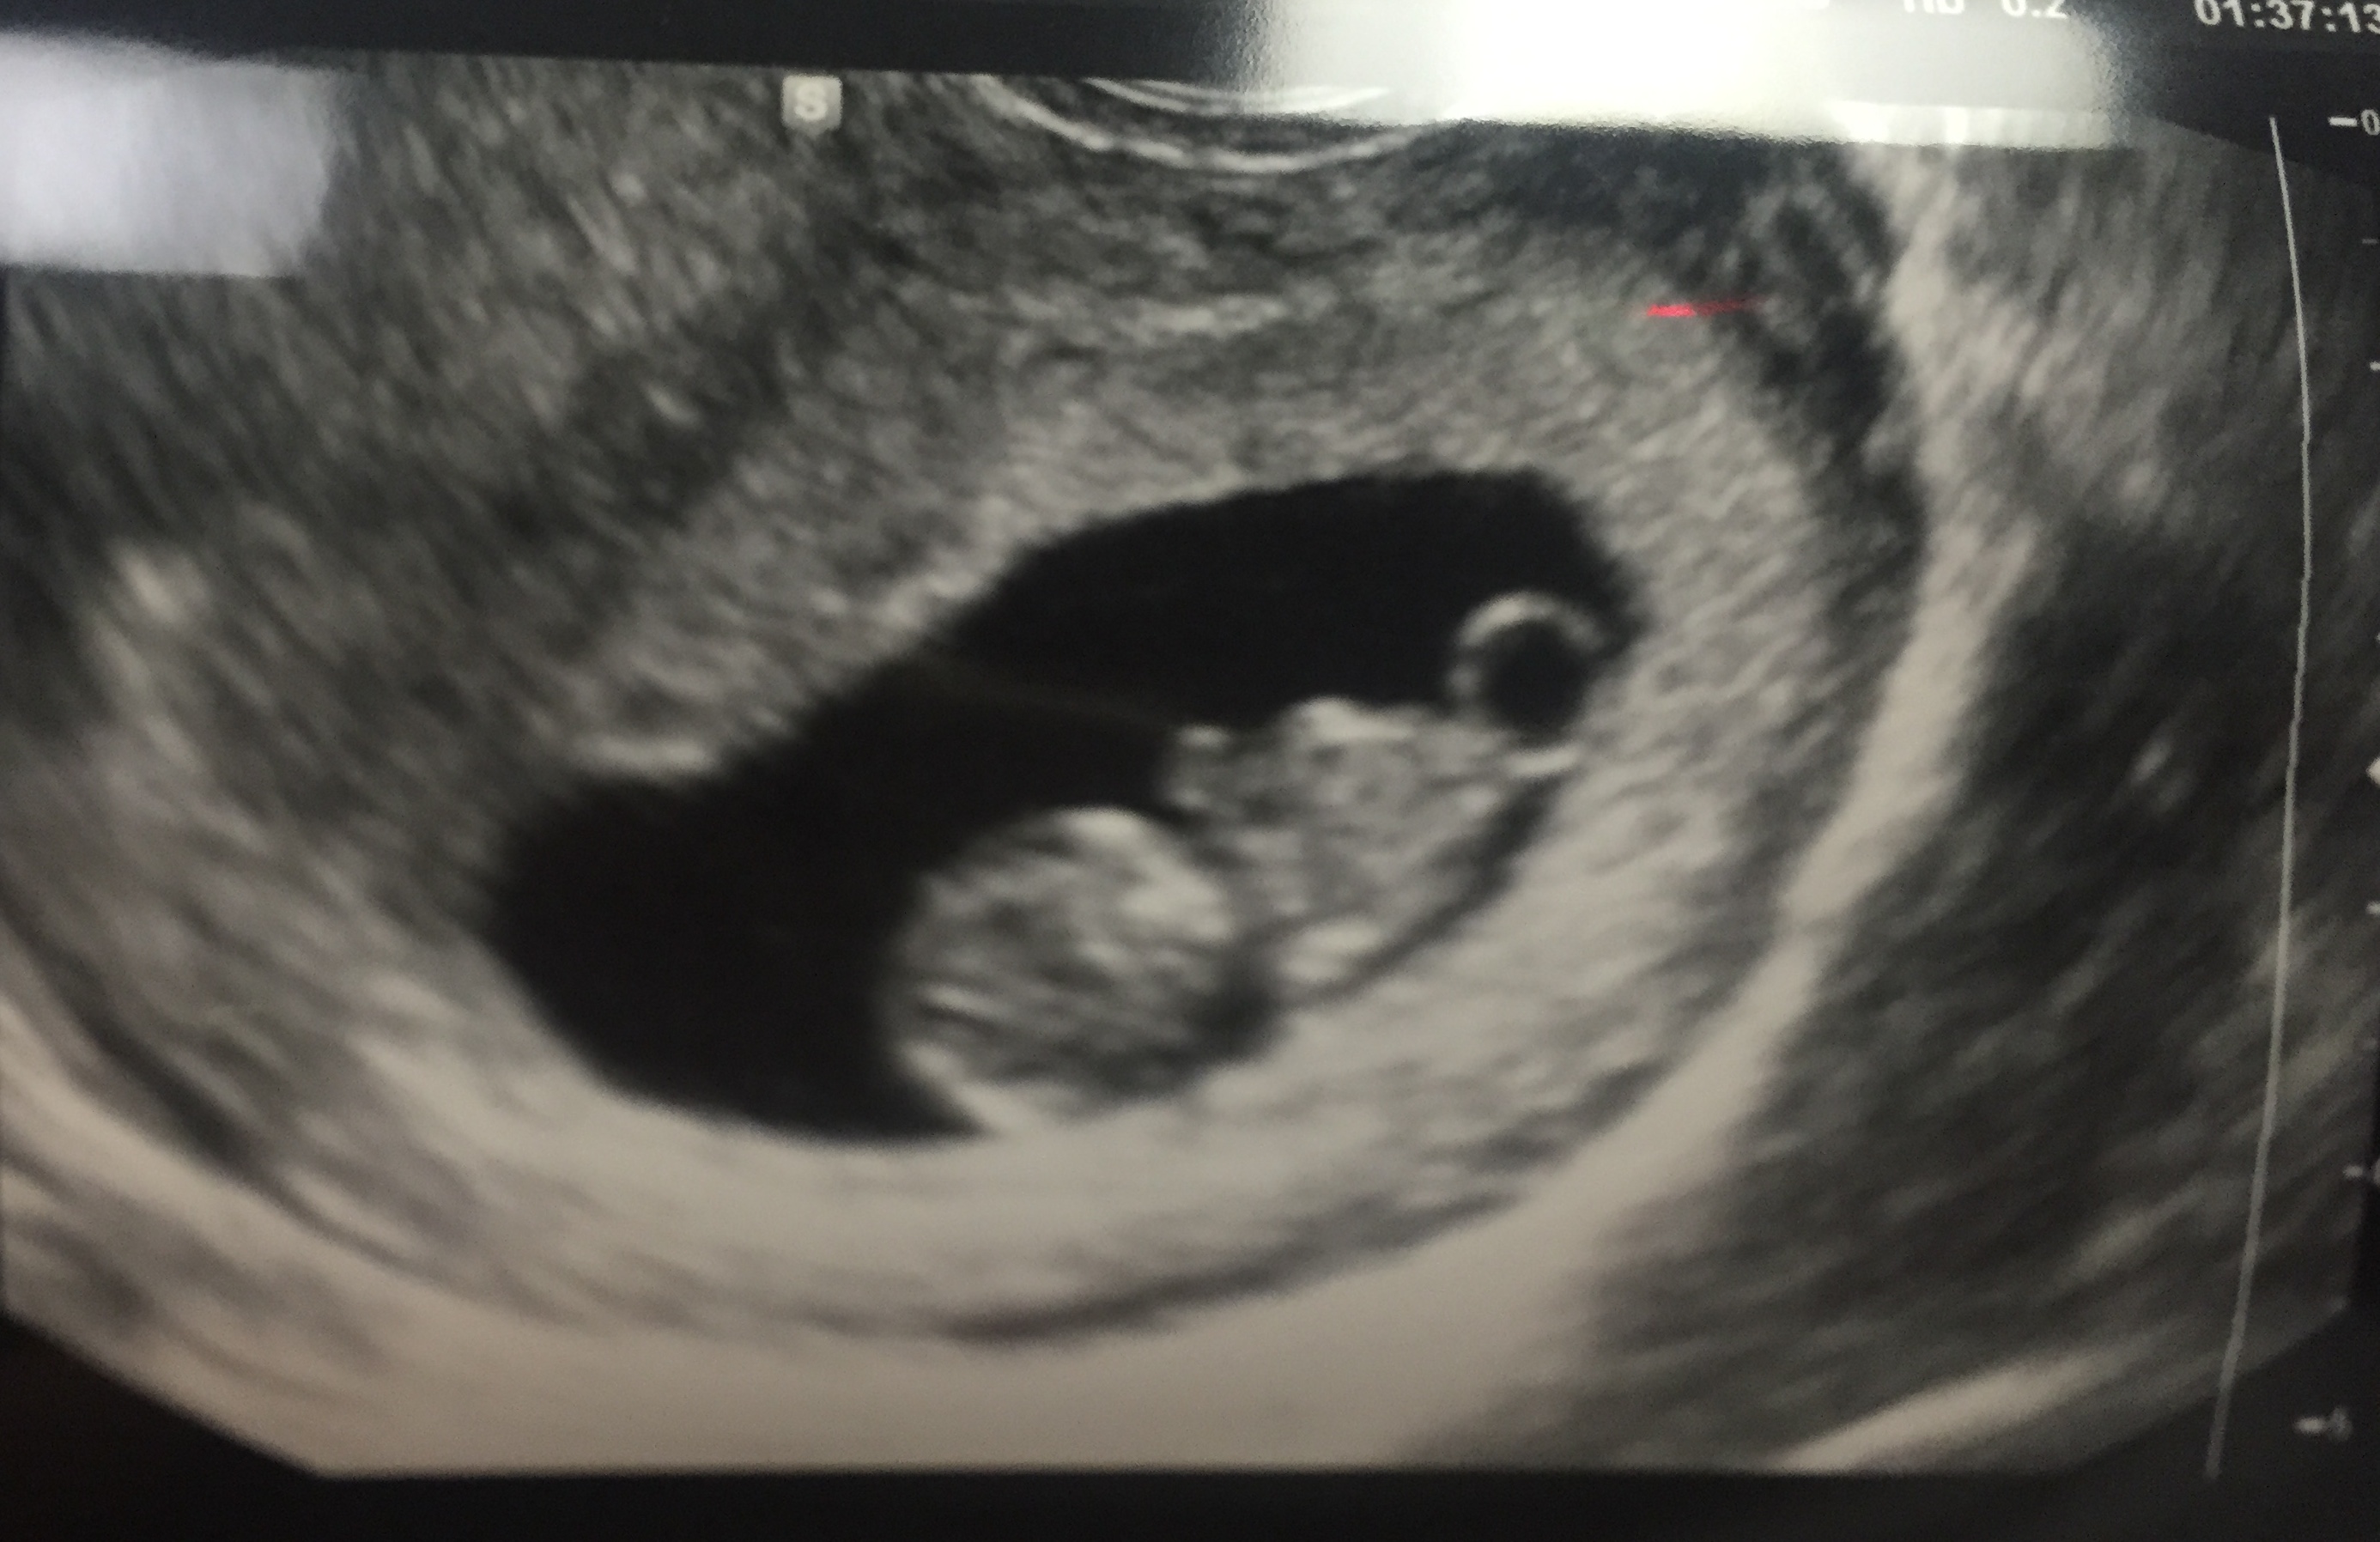

Finally had our ultrasound yesterday. 9 weeks exactly! HB is 163 BPM. I was so nervous walking into that room that something may have been wrong. I am so thankful and feel so blessed that our baby is healthy! :x :x

9 weeks 5 days. Got to see bean's heartbeat and a little movement!!! Idk what was sweeter, seeing the movement or the look on my husband's face when it happened! I'm on cloud 9 today!